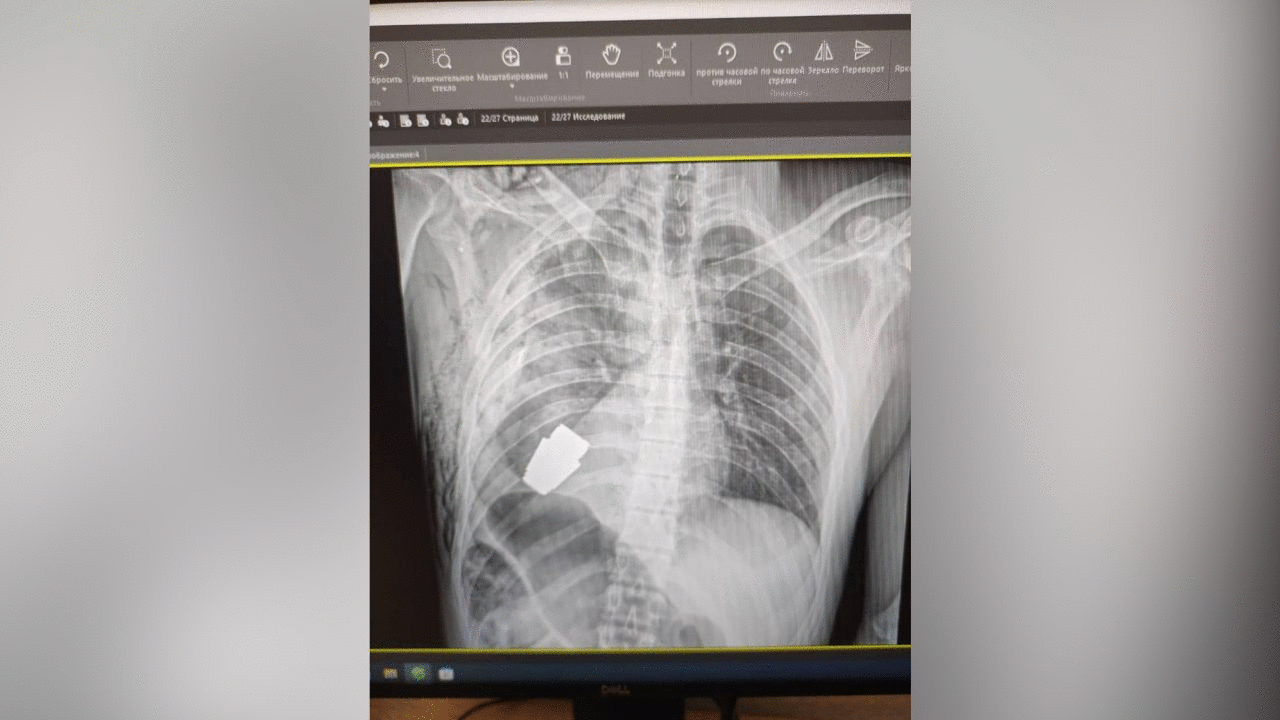

وتضمنت الصور التي جرى نشرها على صفحة "المسعفون العسكريون الأوكرانيون" في موقع "فيسبوك" صورة بالأشعة السينية للجزء العلوي من جسد الجندي مع ظهور القنبلة اليدوية، وفقا للحرة.

ووفقًا للمصدر، فإن المتفجرة التي كانت داخل جسد الجندي عبارة عن قنبلة "VOG"، وهي عبارة عن قنبلة بطول 4 سم تُطلق من قاذفة قنابل يدوية، ومصممة للانفجار فوق الأرض مباشرة، وقادرة على قطع مسافة 400 متر تقريبًا.